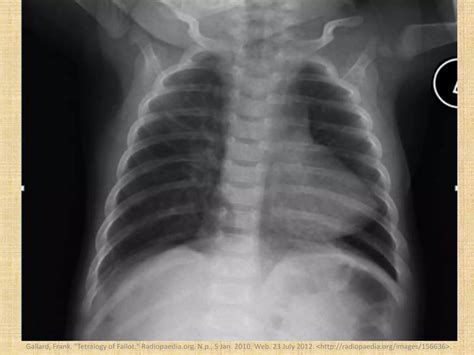

• xray boot shaped heart

• tetralogy of fallot

• boot shaped heart radiology

• tetralogy of fallot radiopaedia